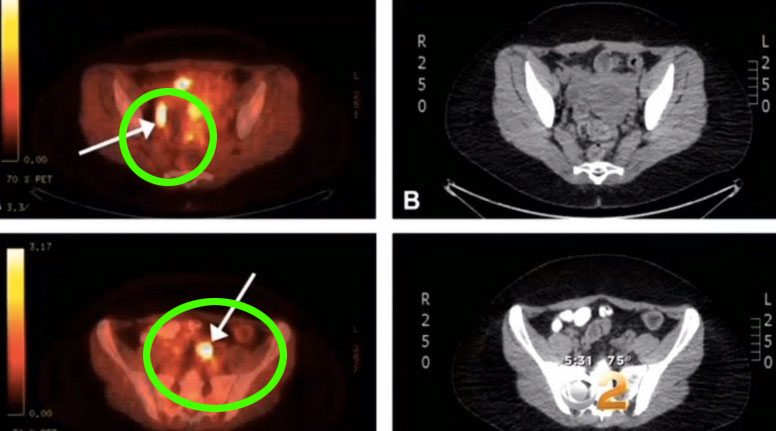

Una madre de cuatro hijos de California recibió el resultado de un escáner PET antes de programarla para la extirpación de sus órganos reproductivos, pues parecía que su cáncer de cuello uterino se había propagado hasta la pelvis.

Los médicos siguieron adelante con el plan para la cirugía, sin embargo, al examinar los ganglios linfáticos, los doctores descubrieron que las células que habían sido brillantemente localizadas en la exploración y que les llevaron a creer que su cáncer se había extendido, no eran cancerosas en absoluto.

¿Qué era entonces lo que estaba pasando? Las células que se iluminaban en el área pélvica eran en realidad depósitos de tinta de los múltiples tatuajes que tenía en sus piernas.

«Esos ganglios linfáticos que se iluminaban brillantemente en la exploración PET lo hacían a causa del pigmento del tatuaje que tenía en los ganglios linfáticos«, dijo su médico.